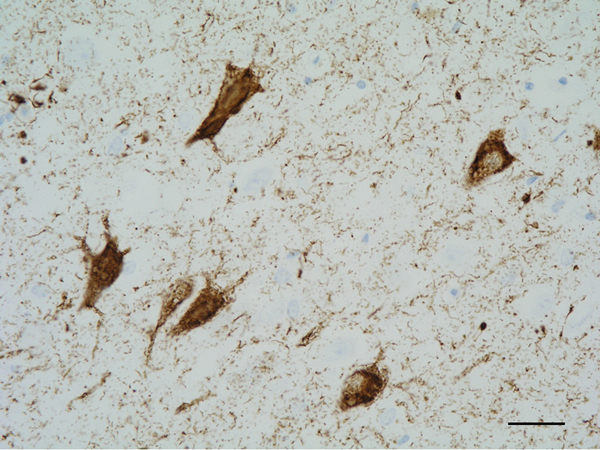

The main constituent of NFTs dystrophic neurites of SPs and neuropil threads is abnormal tau (158-173) (Figures 5, 6, and 7). A combination of all six hyper-phosphorylated brain tau isoforms (3Rtau and 4Rtau expressed in brain), generated from alternative tau splicing, is characteristic of AD tau (163, 174, 175). The amount of 3Rtau is similar to 4Rtau in the human adult brain and in AD. However, possible variations in the ratio of 3Rtau/4Rtau among cell types in the human brain have not been adequately assessed. Abnormal tau in AD includes several species resulting from hyper-phosphorylation at different sites, acetylation, glycosylation, altered confor mation, truncation at glutamic acid 391 and at aspartic acid 421 (mediated by caspase 3), oligomerization, and β-sheet-rich fibril aggregation, among others (171-173, 176-196). The site of tau phosphorylation and other post-translational modifications in tau have commonalities and differences among tauopathies (197, 198). Tau inclusions in glial cells are not found in AD, unless accompanied by other tau co-morbidities including aging-related tau astrogliopathy (ARTAG) and argyrophilic grain disease (AGD) which are 4Rtau-only tauopathies.